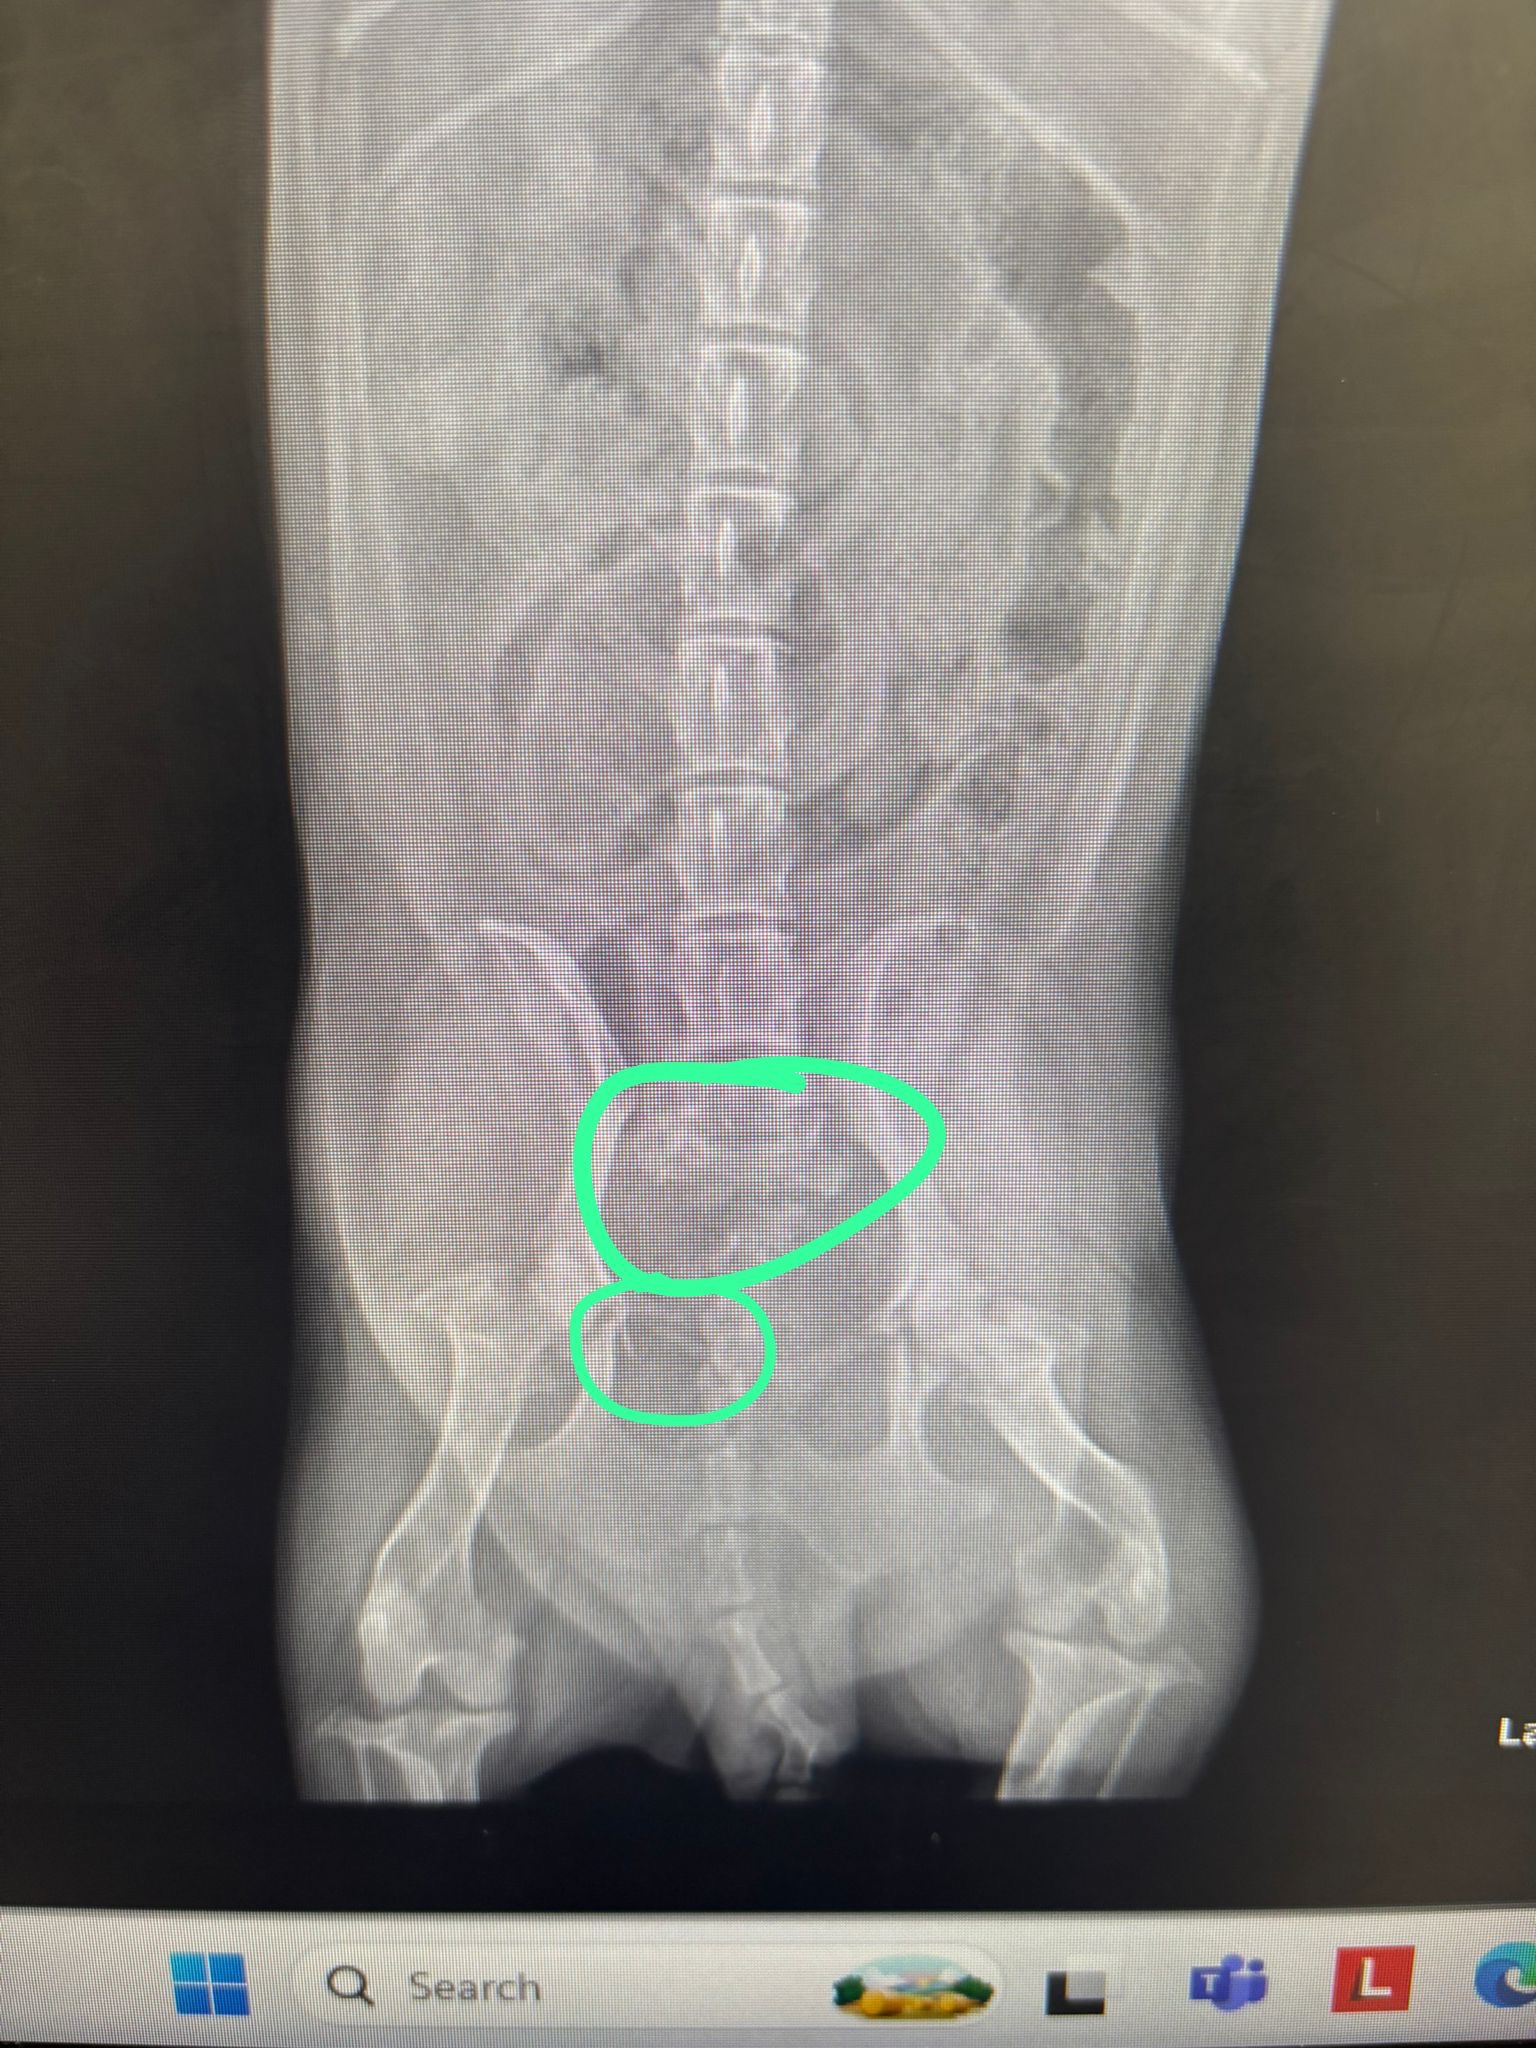

Un conductor la vio, bajó la velocidad y una testigo que venía del carril contrario le advertía que se detuviera. Sin embargo, no hizo caso: la goma delantera la tocó y la trasera terminó aplastando su pelvis, causándole tres fracturas graves en esa área, en la columna y en la cola. Hershey quedó inmóvil y el conductor huyó de la escena, mientras los demás carros que venían en la calle sí se detuvieron.

Necesita dos cirugías que son más de $10,000 USD sin contar el costo de hospitalización que por noche son mas de $400. Debido a la exageración de estas cantidades hemos decidido no proceder con las cirugías y llevarla a casa para que se recupere. El veterinario nos indica que puede tomar varias semanas la recuperación sin cirugías y veremos si puede volver a caminar o no. Solo pedimos colaboración para los gastos que se han hecho en hospitalización, medicamentos y terapias que estará tomando.